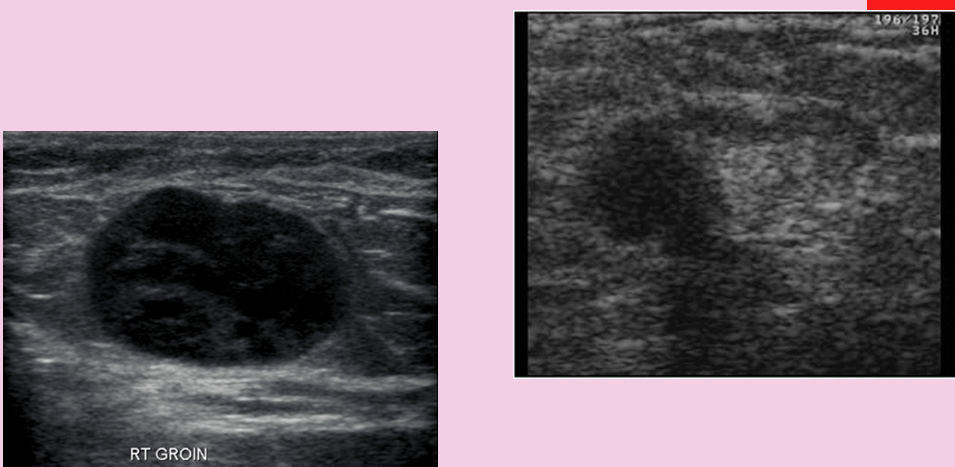

what is this?

enlarged groin lymph node

muscle injury/bakers cyst